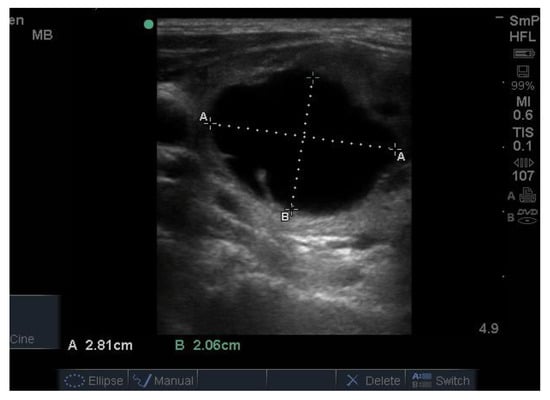

14. Parathyroid Disease

Because the senior author (JW) routinely measures serum calcium, parathyroid hormone (PTH) and vitamin D in his patients, hyperparathyroidism due to a benign adenoma of one of the parathyroid glands appears to be much more common than previously thought. The parathyroid glands are hidden behind the thyroid and so may be obscured by thyroid nodules, although they can often be seen in the longitudinal view below the lobes, as a hypoechoic lesion of around 1 cm in diameter (Figure 18).

Figure 18.

Thyroid ultrasound from a patient with hyperparathyroidism showing a hypoechoic lesion below the right thyroid lobe that was confirmed to be a parathyroid adenoma at surgery.

The parathyroid adenoma is typically hypoechoic by comparison to the nearby thyroid tissue, which is consistent with the author’s experience. However, only about 50% of subsequently proven parathyroid adenomas are seen on ultrasound and even the Sestamibi nuclear scan fails to pick them up in about 30% of cases.